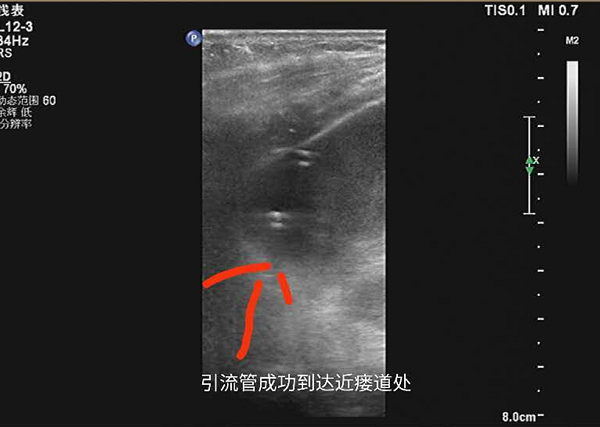

成功穿刺引流

4月9号下午四点,在完善各种医疗文书工作以及各项术前准备后,李嘉医生在B超引导下对患者行腹腔多发脓肿精准穿刺引流。该院B超室团队细致、耐心地引导穿刺导丝以及穿刺针成功地在不到1.3cm的间隙中,避开了肠道以及右肝外叶,将5mm的引流导管头部精准引导入肝下脓肿处。同时引流导管侧孔无偏差地对准于肝肾隐窝脓肿处,精确地引流出两处脓肿,完美地达到术前既定方针。

引流管走向示意图,避开右肝下缘、肠道